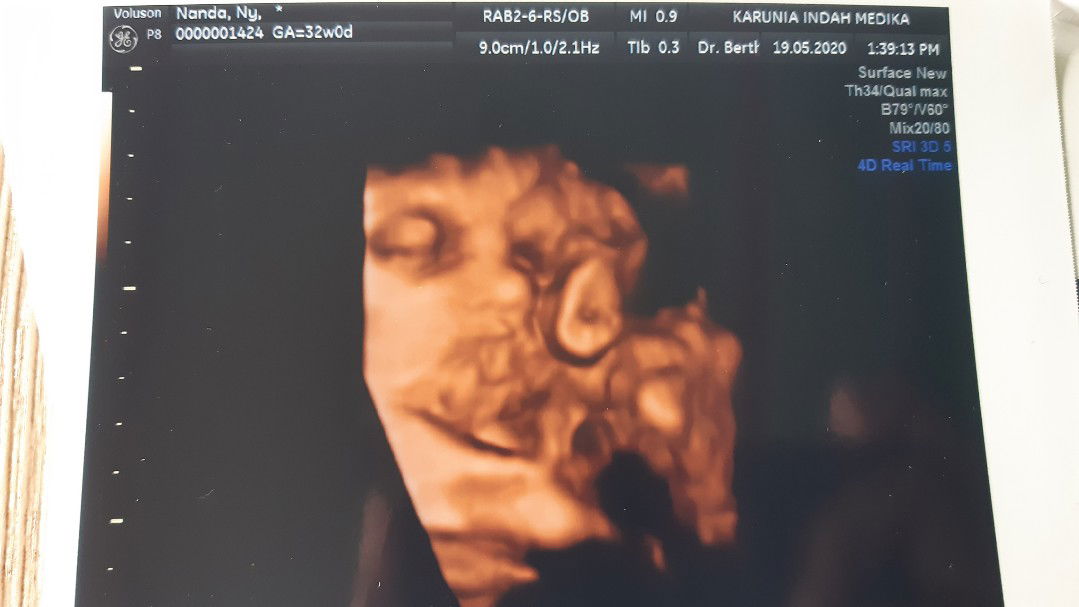

HPL Oktober

Ibu hamil